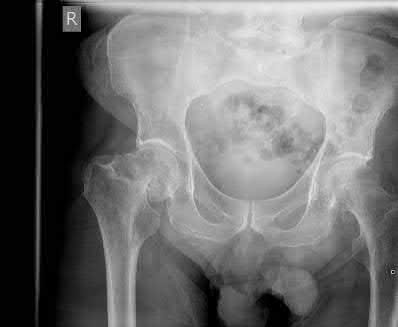

A 27 year-old patient sustains a fracture-dislocation of the acetabulum. Pelvic radiographs (Figures A and B) are taken at initial presentation and a CT scan (Figures C and D) is performed after reduction of the hip in the emergency room. What is the importance of the finding highlighted in the CT scan cuts?

The CT images shown in Figures C and D display significant marginal impaction of the joint surface.

Marginal impaction is common in posterior wall fractures and fracture-dislocations. Critical review of CT imaging of posterior wall fractures can help with preoperative planning for identifying impaction of the articular surface of the acetabulum. Restoration of the sphericity of the acetabulum to match that of the femoral head is important for successful outcome following ORIF of posterior wall fractures. A common surgical technique to accomplish joint surface restoration includes freeing the impacted articular segments, bone grafting of the void created to support the articular segments, and buttress plating of the posterior wall fracture fragments.

Patel et al. discuss the challenge of interpreting imaging of the acetabulum for assessing fracture characteristics that may significantly impact success or surgical intervention. These characteristics include: articular displacement, marginal impaction, incongruity of the joint surface, intra-articular fragments, and osteochondral injury to the femoral head. Based on expert review of images, determination of significant marginal impaction had a poor intraobserver reliability, as did each of the other modifiers listed.

Figures A and B are radiographs of the posterior wall fracture and hip dislocation. They do not show the large amount of marginal impaction of the acetabular surface. Figure C (coronal reconstruction) and Figure D (sagittal reconstruction) point out a large a amount of marginal impaction of the acetabular. Note the disruption of the joint surface on the intact portion of the acetabulum.